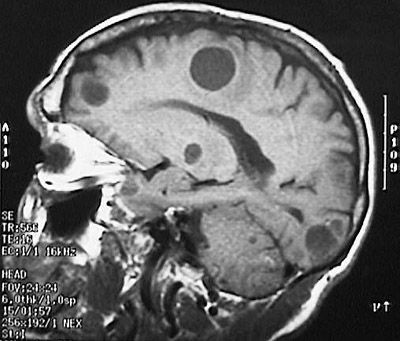

Click on a metastasis in the MRI scan above:

This magnetic resonance imaging (MRI) scan of the head in sagittal view reveals the presence of several well-circumscribed metastatic tumor nodules of the brain.